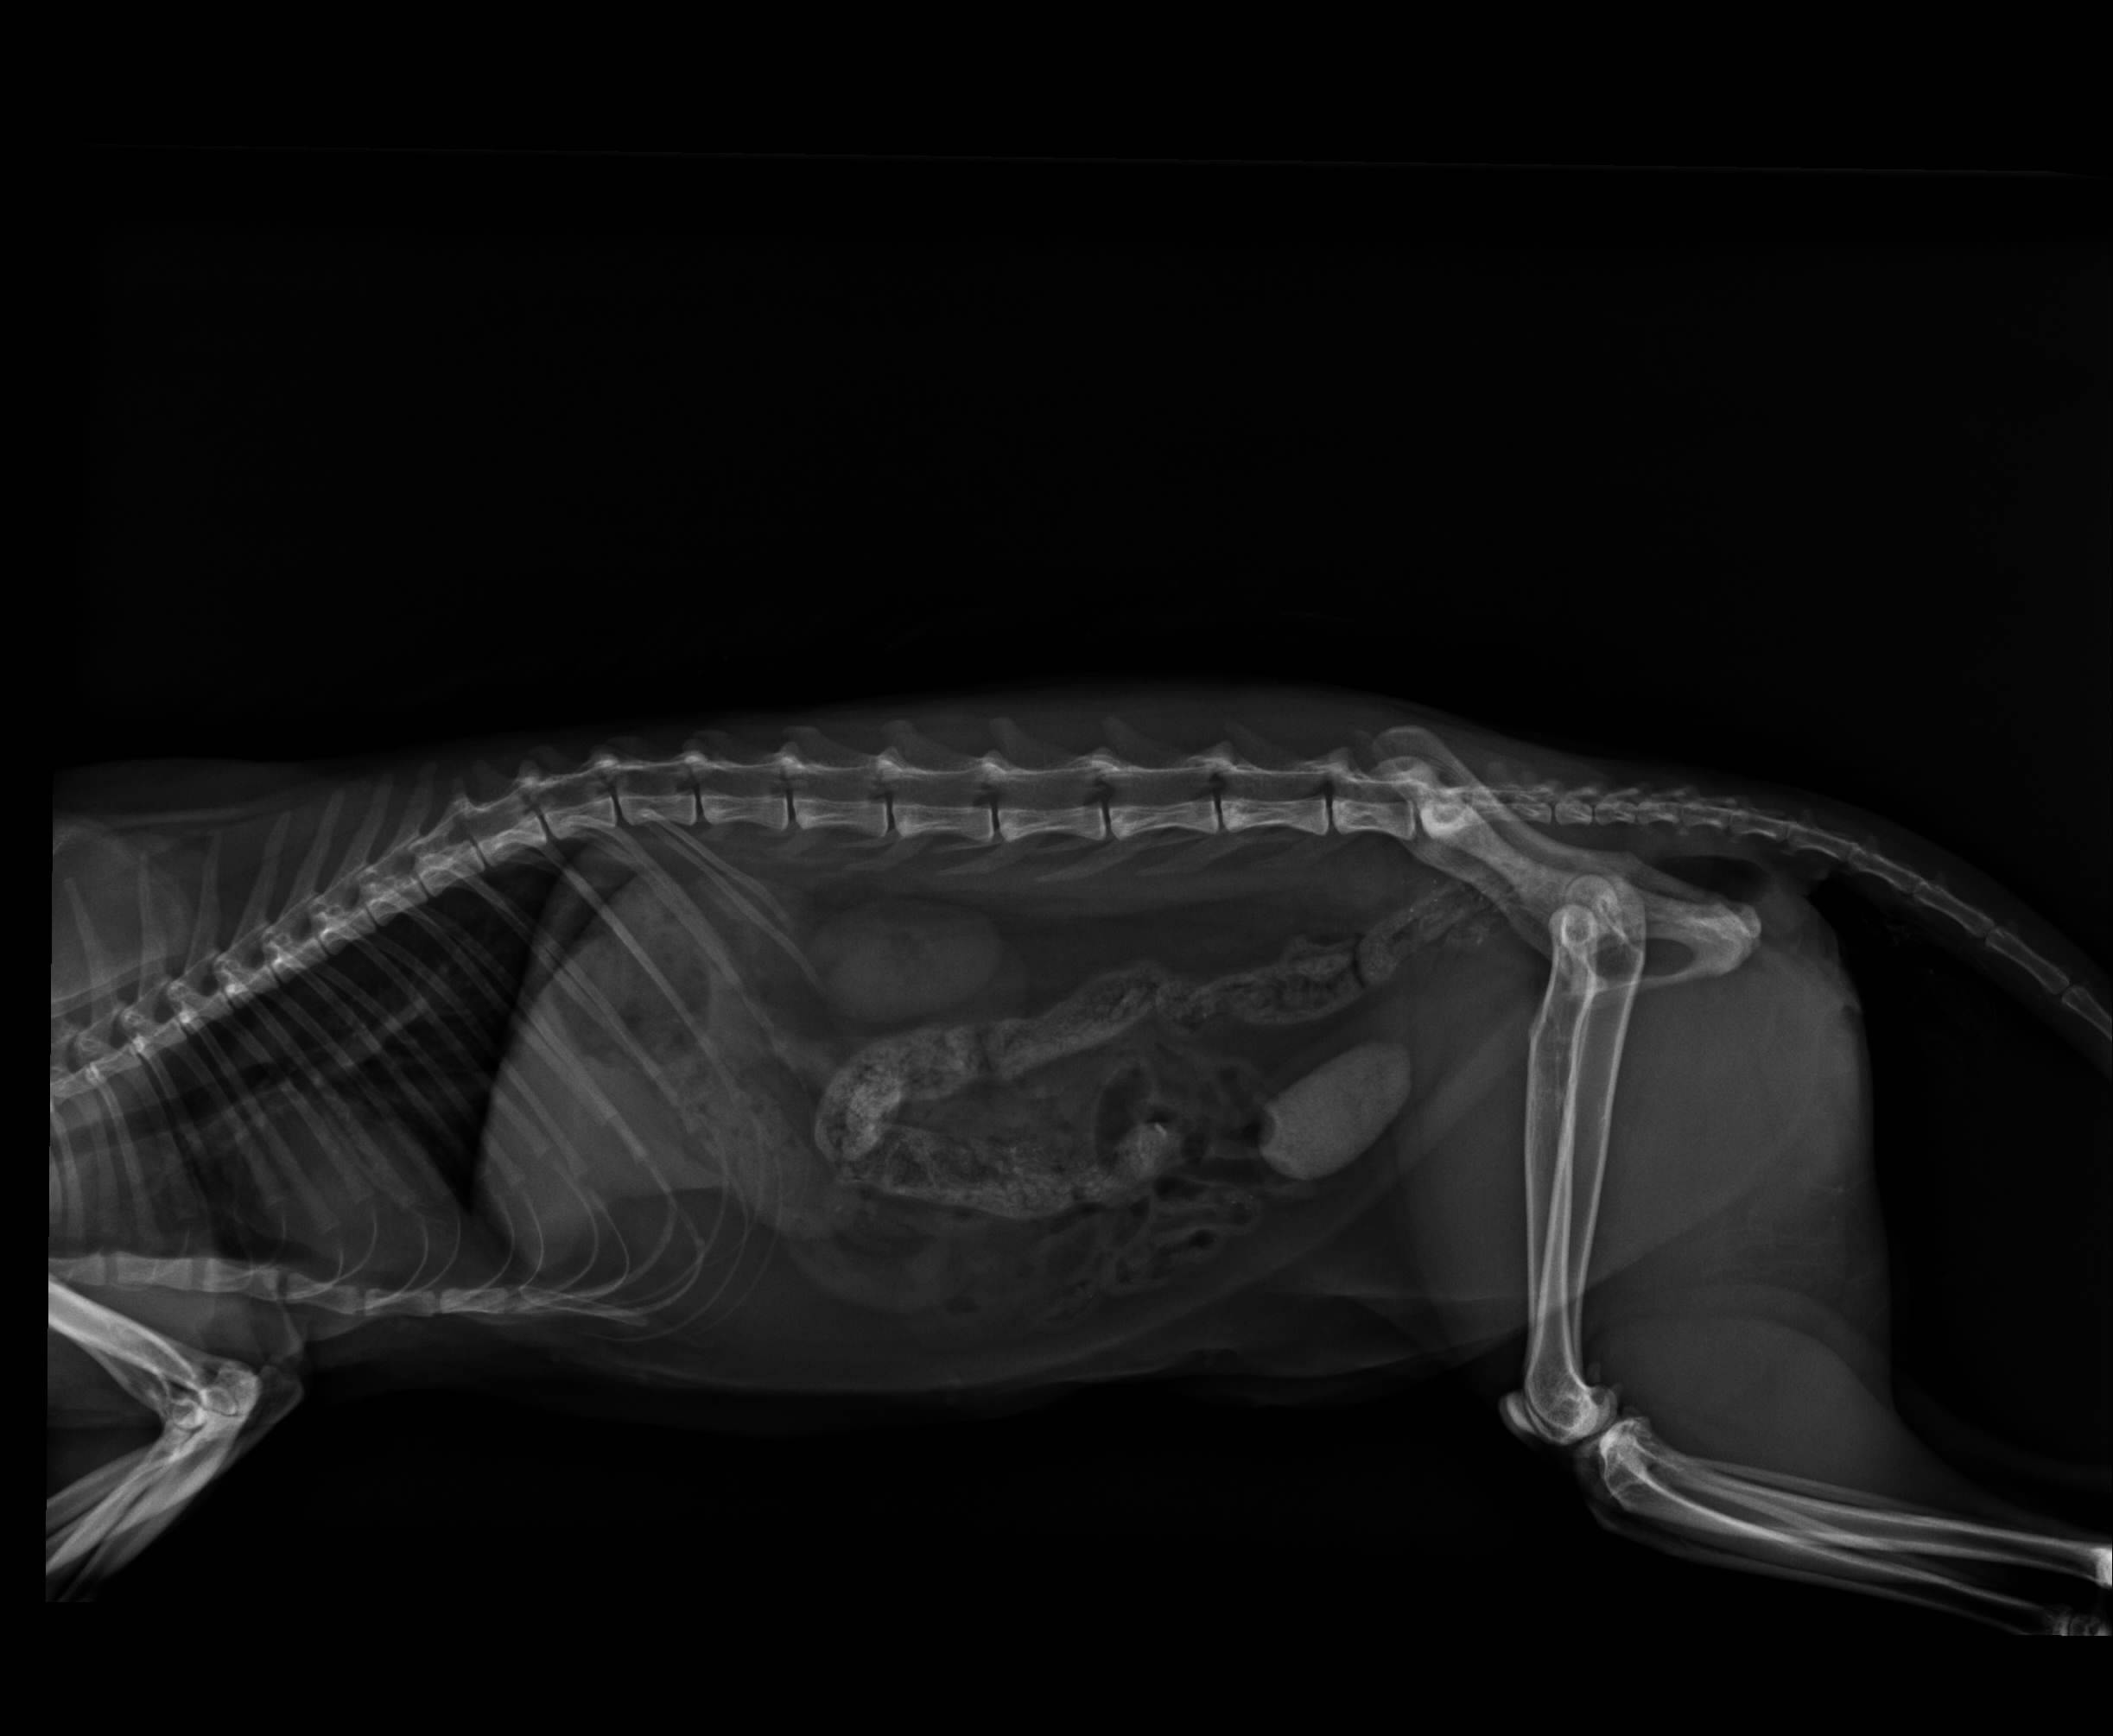

在醫生細心檢查後.尿道口膿樣分泌物經X-ray檢查發現有一直徑3cm結石,並手術取出,目前貓咪的復原狀況良好,為節省住院開消,貓咪已由志工接回照顧,待傷口與體力恢復至最佳狀態,會再放回原地.

4.X光檢查 400